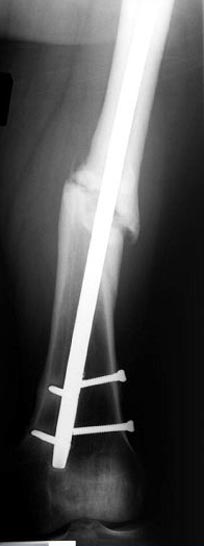

Аппарат Илизарова= Taylor spatial frame

Операцию провели в два этапа, сперва удалили штифт, рассверливание римером на пару мм большего диаметра, определение чувствительности на анаэробную и аэробную культуру (где исследования показали негативный результат чувствительности), через дней десять - начали аппаратную фиксацию.

Деформация:

Вальгус- 17 градусов

Рекурватум 5 градусов

Укорочение 2.5см

Ротационно 22 градусов внутренная

Смещение диафиза по поперечнику 75%